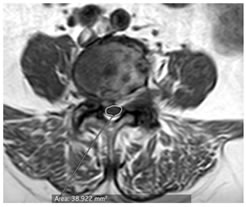

CASE 2

T1 AND T2 W AXIAL IMAGES SHOWING DIFFUSE DISC BULGE WITH SEVERE BILATERAL FACETAL ARTHROPATHY AND LIGAMENTA FLAVA THICKENING AT L5-S1 LEVEL CAUSING MODERATE THECAL SAC STENOSIS, NARROWING OF LATERAL RECESS WITH COMPRESSION OVER BILATERAL TRAVERSING NERVE ROOTS. AN INTRASPINAL SYNOVIAL CYST IS ALSO SEEN ARISING FROM FACET JOINT ON THE RIGHT.

AXIAL T1 AND T2 W IMAGES SHOWING HYPOINTENSE SIGNAL ON PEDICLE OF S1 VERTEBRA ON LEFT SIDE SUGGESTIVE OF SCLEROTIC LESION POSSIBLY OSTEOMA